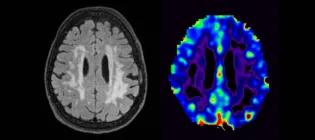

MRI scan showing small vessel disease, a common cause of cognitive impairment.

Senior Clinical Research Fellow

My research focuses on vascular cognitive impairment, dementia trials and how Alzheimer's disease and vascular pathologies interact in dementia.

Tim.Wilkinson@ed.ac.uk